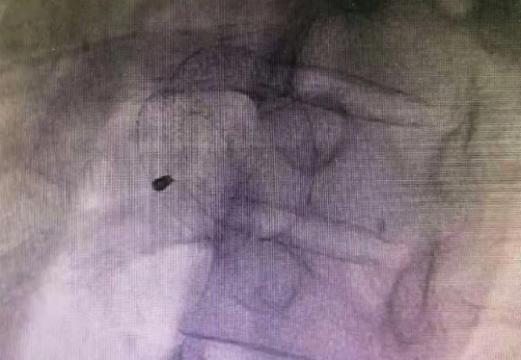

△术中评估

术前准备完善后,心血管内科团队在介入诊疗中心采用新型国产二代封堵器为患者顺利实施“房间隔介入封堵术”,术后三天患者康复出院。